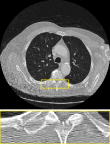

MRI We evaluate on the fastMRI brain validation set using the single-coil accelerated acquisition procedure from Zbontar et al. (2018) with acceleration factors and . The problem is formulated as , where is a binary mask and the discrete Fourier transform, and . Quantitative results are reported in Table 2 and visuals in Figure 7. The proposed RAM model outperforms all baselines.

Single coil MRI

We provide in Figure 7 visual results for MRI reconstructions on acceleration factors 4 and 8 respectively.

| uDPIR tied | RAM | Ground-truth | ||

| acc. factor 4 | ![]() |

| 0.863 | 0.868 | SSIM | ||

| acc. factor 8 | ![]() |

| 0.831 | 0.840 | SSIM |